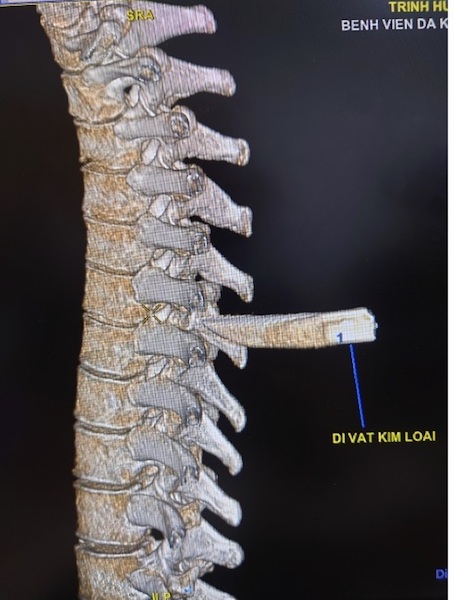

Nam thanh niên 30 tuổi bị dao đâm vào cột sống. Khiến phải mang cả mũi dao cắm sâu vào lưng đến bệnh viện cấp cứu. Các bác sĩ đã phải nhanh chóng lấy mũi dao ra khỏi người bệnh nhân.

Chiều 8/4, tin từ bệnh viện Đa khoa Trung ương Cần Thơ, các bác sĩ khoa Ngoại Thần kinh đã phẫu thuật cấp cứu lấy thành công mũi dao đâm vào cột sống nam bệnh nhân T.H.T.H, 30 tuổi, ngụ tỉnh Sóc Trăng.

Tình trạng lúc nhập viện, bệnh nhân H. tỉnh, niêm hồng, than đau lưng, khó thở nhẹ với vết thương lưng thành ngực sau cạnh trái cột sống đoạn ngực 4-5 rỉ máu, còn dị vật, không tê yếu chi, dấu hiệu sinh tồn ổn định.

Sau 90 phút phẫu thuật, ê-kíp phẫu thuật gồm: Bs.CK2 Trần Văn Minh – Phó Trưởng, khoa Ngoại Thần kinh, Bs. Nguyễn Châu Thanh, Bs.CK1 Nguyễn Văn Vĩnh – Khoa Phẫu thuật – Gây mê hồi sức đã lấy thành công mũi dao dài 5x2cm ra ngoài.

Theo Bs.CK2 Trần Văn Minh, may mắn là trường hợp này mũi dao chưa gây vết thương tủy sống, nếu tổn thương tủy sống bệnh nhân sẽ có rối loạn cảm giác, rối loạn vận động, liệt tủy không hoàn toàn với các biến chứng dò dịch não tủy, nhiễm trùng, áp xe, viêm màng não tủy.